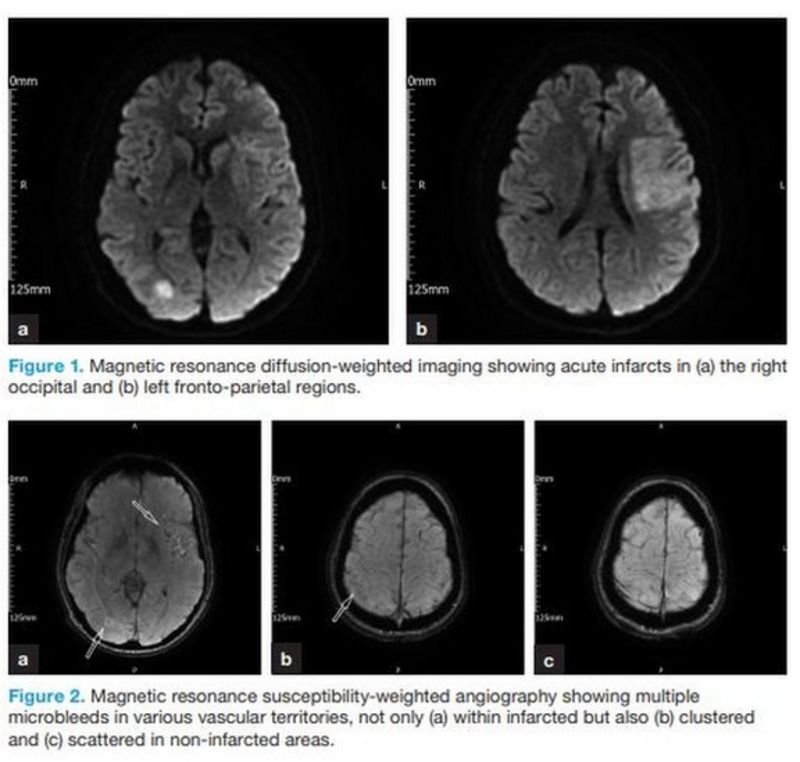

Лекарите са изследвали мозъка на баща на две деца, който е станал най-младият пациент в света с инсулт поради коронавирус.

31-годишният Омар Тейлър прекара шест седмици в болница в Колчестър с коронавирус, пневмония, сепсис, дихателна недостатъчност и инсулт.

Случаят е помогнал на медиците да разберат влиянието на вируса върху мозъка.

Консултантът по инсулт д-р Джоузеф Нге се грижи за г-н Тейлър и е съавтор на доклада за British Journal of Hospital Medicine.

Той каза, че се надява, че това повишава информираността за потенциалния риск пациентите с Covid-19 да получат инсулт.

„Омар е най-младият пациент, който сме открили в медицинската литература и е получил инсулт, причинен от вируса“, ​​каза той.

„Случаят му е много интригуващ и ще го помня до края на живота си.

"Ние научаваме повече за вируса всеки ден и сега знаем, че той може да предизвика възпалителна реакция, която може да доведе до инсулт, дори при много млади пациенти, като Омар."

Изображенията на мозъка на г-н Тейлър показват необичайни характеристики при толкова млад пациент, който не е имал предишни рискови фактори за инсулт, добави той, като "множество микрокръвоизливи" предполагат индуцирана от Covid-19 "цитокинова буря".

„Той получи най-тежкия инсулт, който можете да получите, и мозъкът му беше атакуван от двете страни“, каза д-р Нге. "По-голямата част от пациентите ще се нуждаят от 24-часова грижа след този вид инсулт."